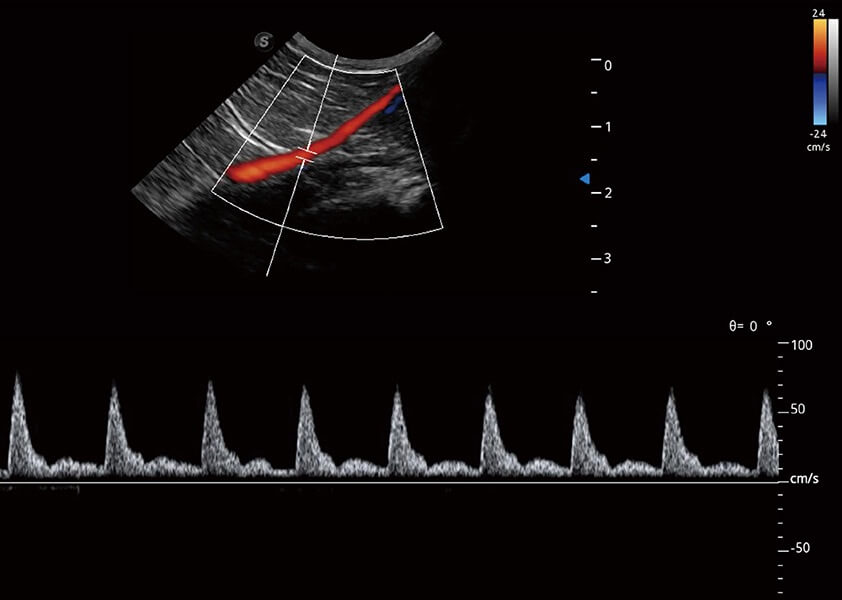

ProPet 60 作为一款高端台式动物超声设备,为动物医生的日常诊断提供了一系列贴合动物临床需求、解决临床实际问题的高级成像功能。凭借全系列高清探头,满足医生对腹部、心脏、生殖、浅表、肌骨等成像的所有需求,切实帮助您提升检查效率,提高诊断信心。

动物是人类最亲密的朋友和最值得信赖的伙伴。竞技宝(JJB)官方网站也一直致力于探索动物专用的超声影像解决方案。 全新推出的ProPet系列,是竞技宝(JJB)官方网站在动物超声影像智能化、专业化、精准化的一次跨越式革新。动物不能用言语来表述自己的不适,通过超声影像,ProPet系列搭建了动物医生与不同物种沟通的“桥梁”,为动物医生注入了“治愈之力”。